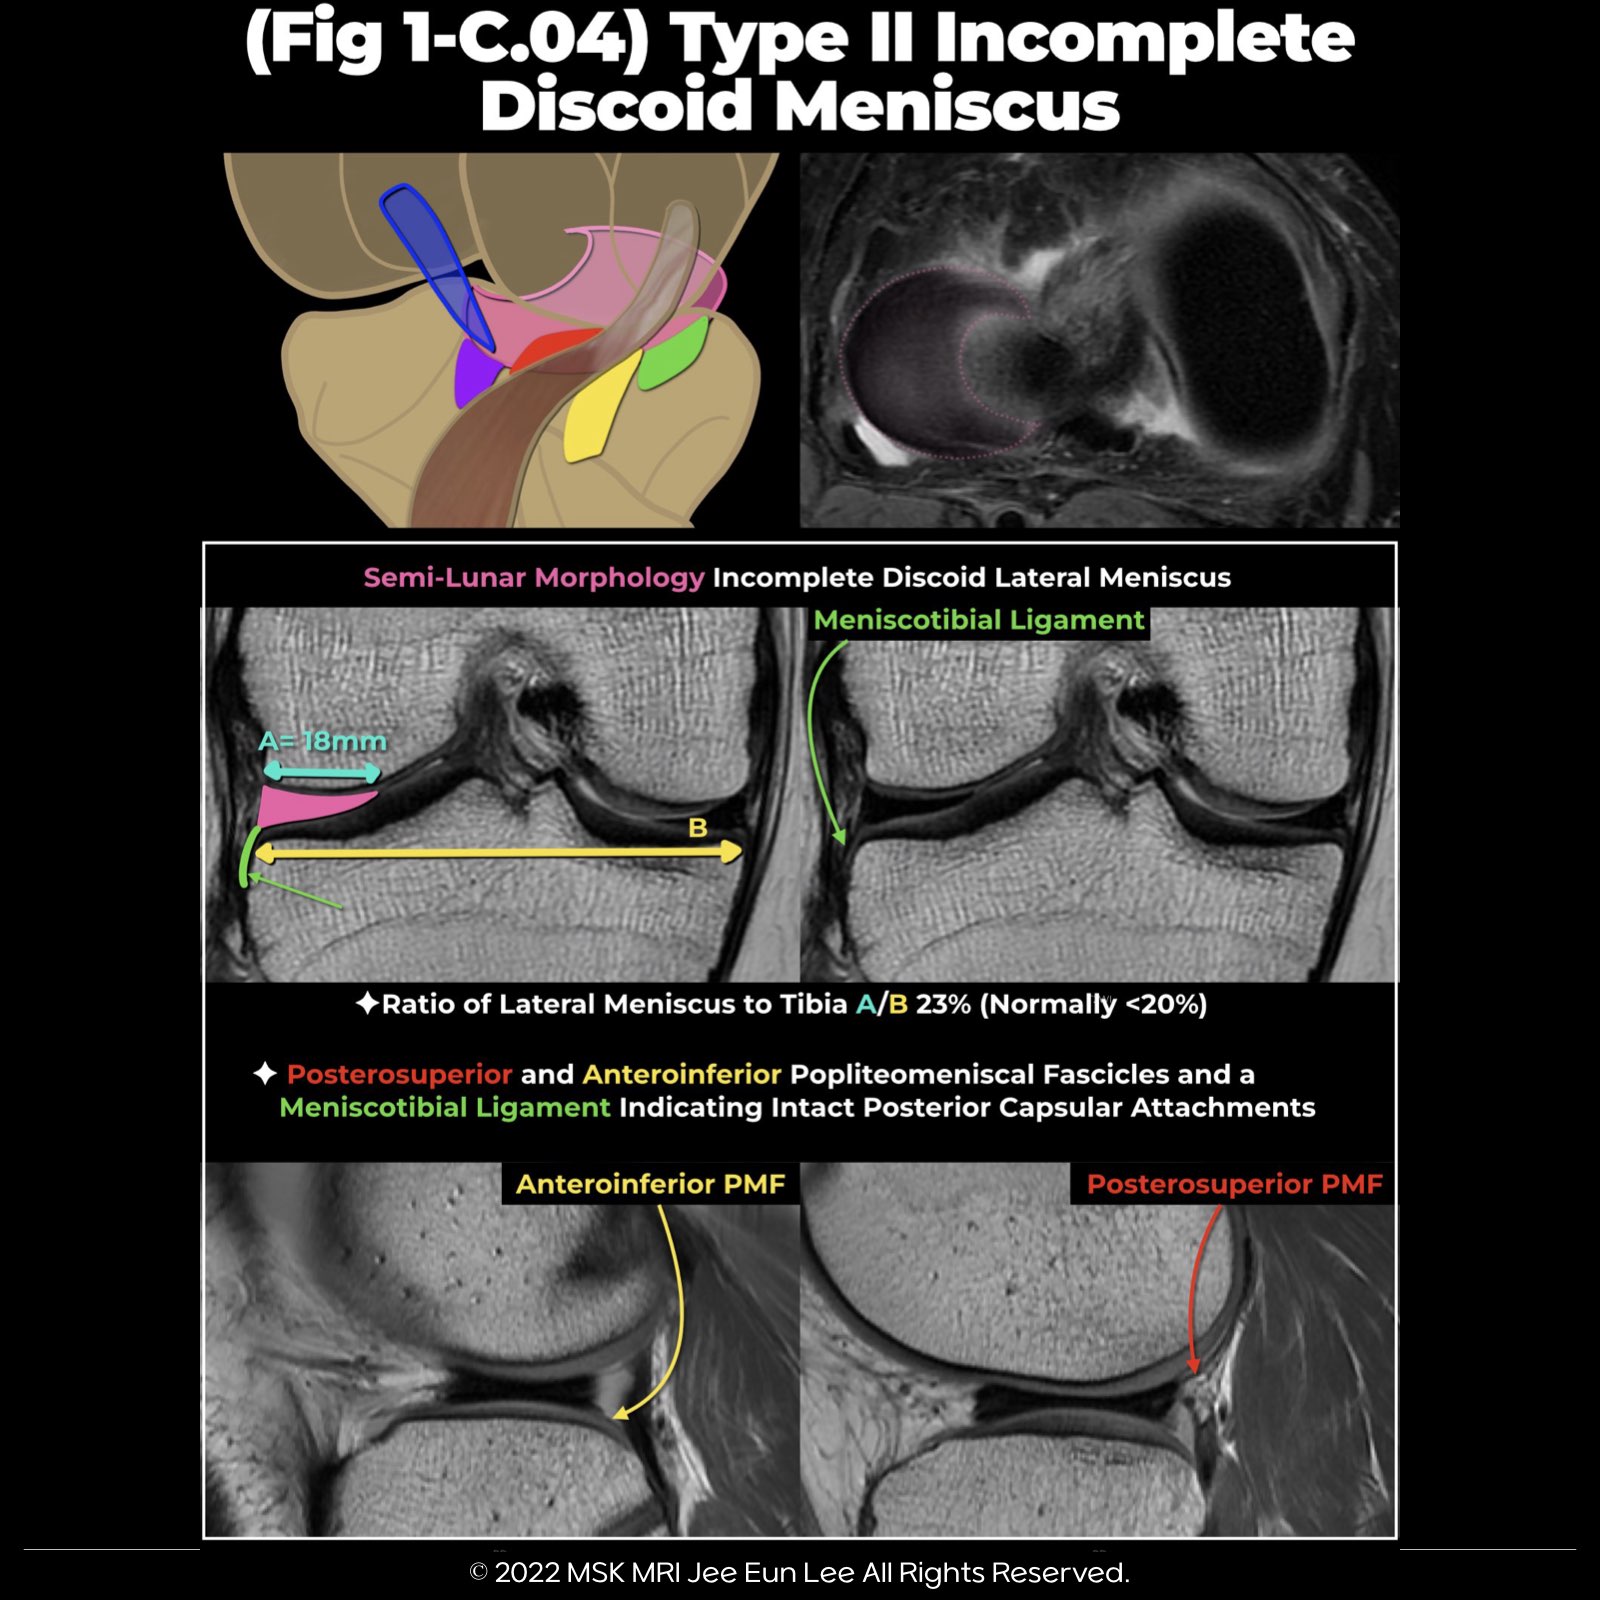

Type II: partial or incomplete discoid lateral meniscus

A partial or incomplete discoid lateral meniscus that has a semi-lunar morphology, covering up to 80% of the surface of the lateral tibial plateau, with a normal posterior capsular attachment

- The ratio of lateral meniscus-to-tibia (RMT) width is a more accurate method to determine the presence of a discoid lateral meniscus on MRI.

- The ratio of the minimal meniscal width to the maximal tibial width of more than 20% may be used.